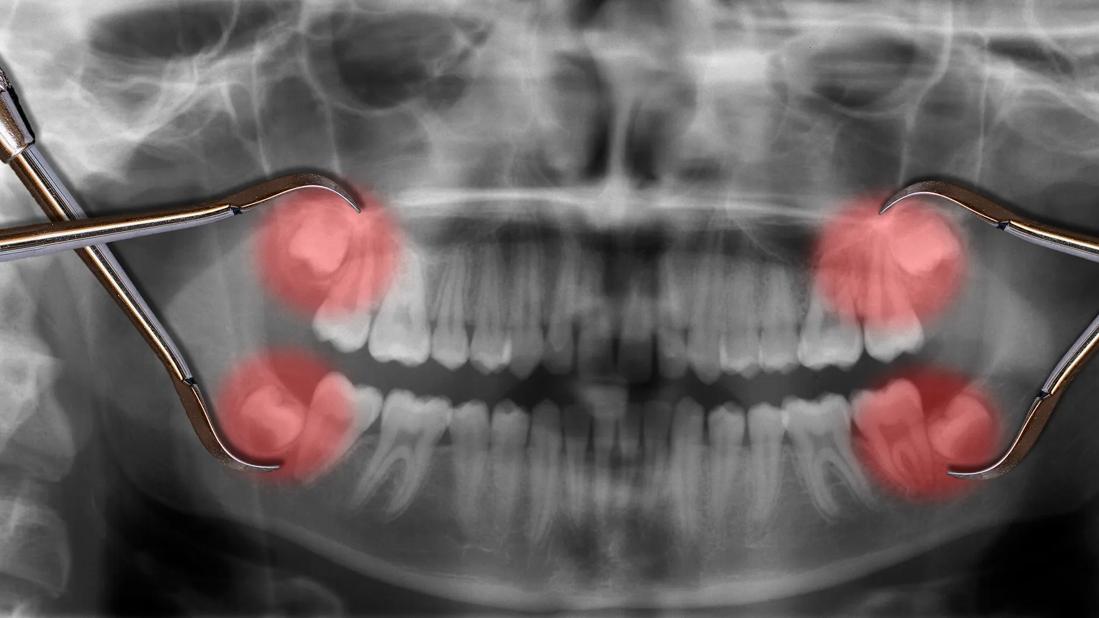

X-ray of teeth, with wisom teeth highlighted red, with dental tools on top of X-ray

Wisdom teeth pop up through your gums behind your second molars, usually between the ages of 17 and 25. If you have a full set of four, each wisdom tooth resides in a different quadrant of your jaw. (That’s upper left, lower left, upper right and lower right, if you’re mapping it out.)

Gum tissue often becomes sensitive, swollen and inflamed around impacted wisdom teeth. Impacted wisdom teeth are essentially trapped in your gums or jawbone. Teeth that are partially or completely buried instead of fully erupted often lead to oral health problems.

Impacted wisdom teeth are common and affect about 90% of people with wisdom teeth. Dentists generally evaluate impacted teeth on a case-by-case basis to determine whether to recommend removal.